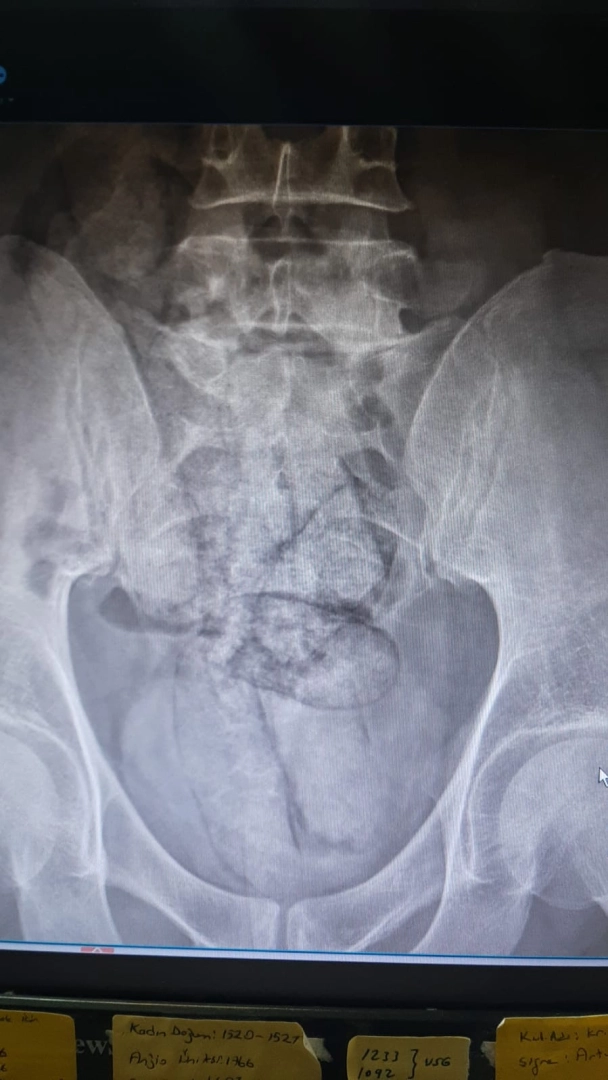

ARTVİN, (DHA)- ARTVİN’de bağırsağından 350 gram metamfetamin çıkan İran uyruklu F.R. (43) gözaltına alındı.İl jandarma ekipleri, takip ettikleri İran uyruklu şüpheliyi dün saat 02.00 sıralarında Çayağzı Mahallesi’nde durdurdu. Üzerinde yapılan aramada herhangi bir olumsuzluğa rastlanmayan F.R., detaylı kontrol için hastaneye götürüldü. Artvin Devlet Hastanesi’nde tomografisi çekilen şüphelinin bağırsaklarında 10 paket halinde uyuşturucu madde taşıdığı belirlendi. Şüphelinin hayati tehlike oluşturabilecek şekilde sakladığı paketler, cerrahi müdahaleyle çıkarıldı. İncelemede paketlerin içinde toplam 350 gram metamfetamin olduğu tespit edildi.Gözaltına alınan şüpheli hakkında adli işlem başlatıldı. (DHA)